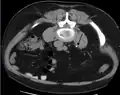

Imaging studies

Calcium-containing stones are relatively radiodense, and they can often be detected by a traditional radiograph of the abdomen that includes the kidneys, ureters, and bladder (KUB film).[58] KUB radiograph, although useful in monitoring size of stone or passage of stone in stone formers, might not be useful in the acute setting due to low sensitivity.[59] Some 60% of all renal stones are radiopaque.[60][61] In general, calcium phosphate stones have the greatest density, followed by calcium oxalate and magnesium ammonium phosphate stones. Cystine calculi are only faintly radiodense, while uric acid stones are usually entirely radiolucent.[62]

In people with a history of stones, those who are less than 50 years of age and are presenting with the symptoms of stones without any concerning signs do not require helical CT scan imaging.[63] A CT scan is also not typically recommended in children.[64]

Otherwise a noncontrast helical CT scan with 5 millimeters (0.2 in) sections is the diagnostic method to use to detect kidney stones and confirm the diagnosis of kidney stone disease.[16][56][60][65][7] Near all stones are detectable on CT scans with the exception of those composed of certain drug residues in the urine,[58] such as from indinavir.

Bilateral kidney stones can be seen on this KUB radiograph. There are phleboliths in the pelvis, which can be misinterpreted as bladder stones.